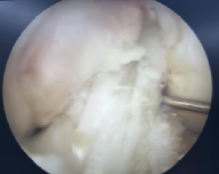

本例患者为28岁年轻女性,因意外摔伤导致左膝关节前交叉韧带完全断裂,辗转当地多家医院咨询后,最终选择前来我科手术。张智主治医师接诊患者后立即向杜恒副主任汇报,并联系尹战海主任共同讨论制定手术方案,最终确定行左膝关节镜检关节清理+半月板成形+自体腘绳肌腱重建前交叉韧带手术。

在尹战海主任的协调指导及消毒供应科的大力配合下,从总院调配关节镜设备及相关手术器械,在麻醉手术部宋珂珂、杨涵钦、李杨、高彤团队的紧密配合下,由张智主治医师主刀顺利完成手术。术后骨科任洁、孙梦媛、习姣等护理团队无缝衔接,确保了围术期无痛化管理和加速康复。术后4小时即开始无痛自主锻炼,术后1天拄拐患肢不负重活动,术后4天被动屈膝轻松达到90度,今日顺利出院继续院外康复。

2025年1月10日,我院骨科陆港院区再接再厉,单日又完成3例关节镜微创手术。分别为13岁女性外侧盘状半月板撕裂患者行半月板成形缝合修复术,为21岁男性陈旧性前交叉韧带断裂患者行自体肌腱前交叉韧带重建术,为58岁女性骨关节炎膝关节游离体患者行关节清理游离体取出术。目前这些患者均康复良好,拟于近期出院。